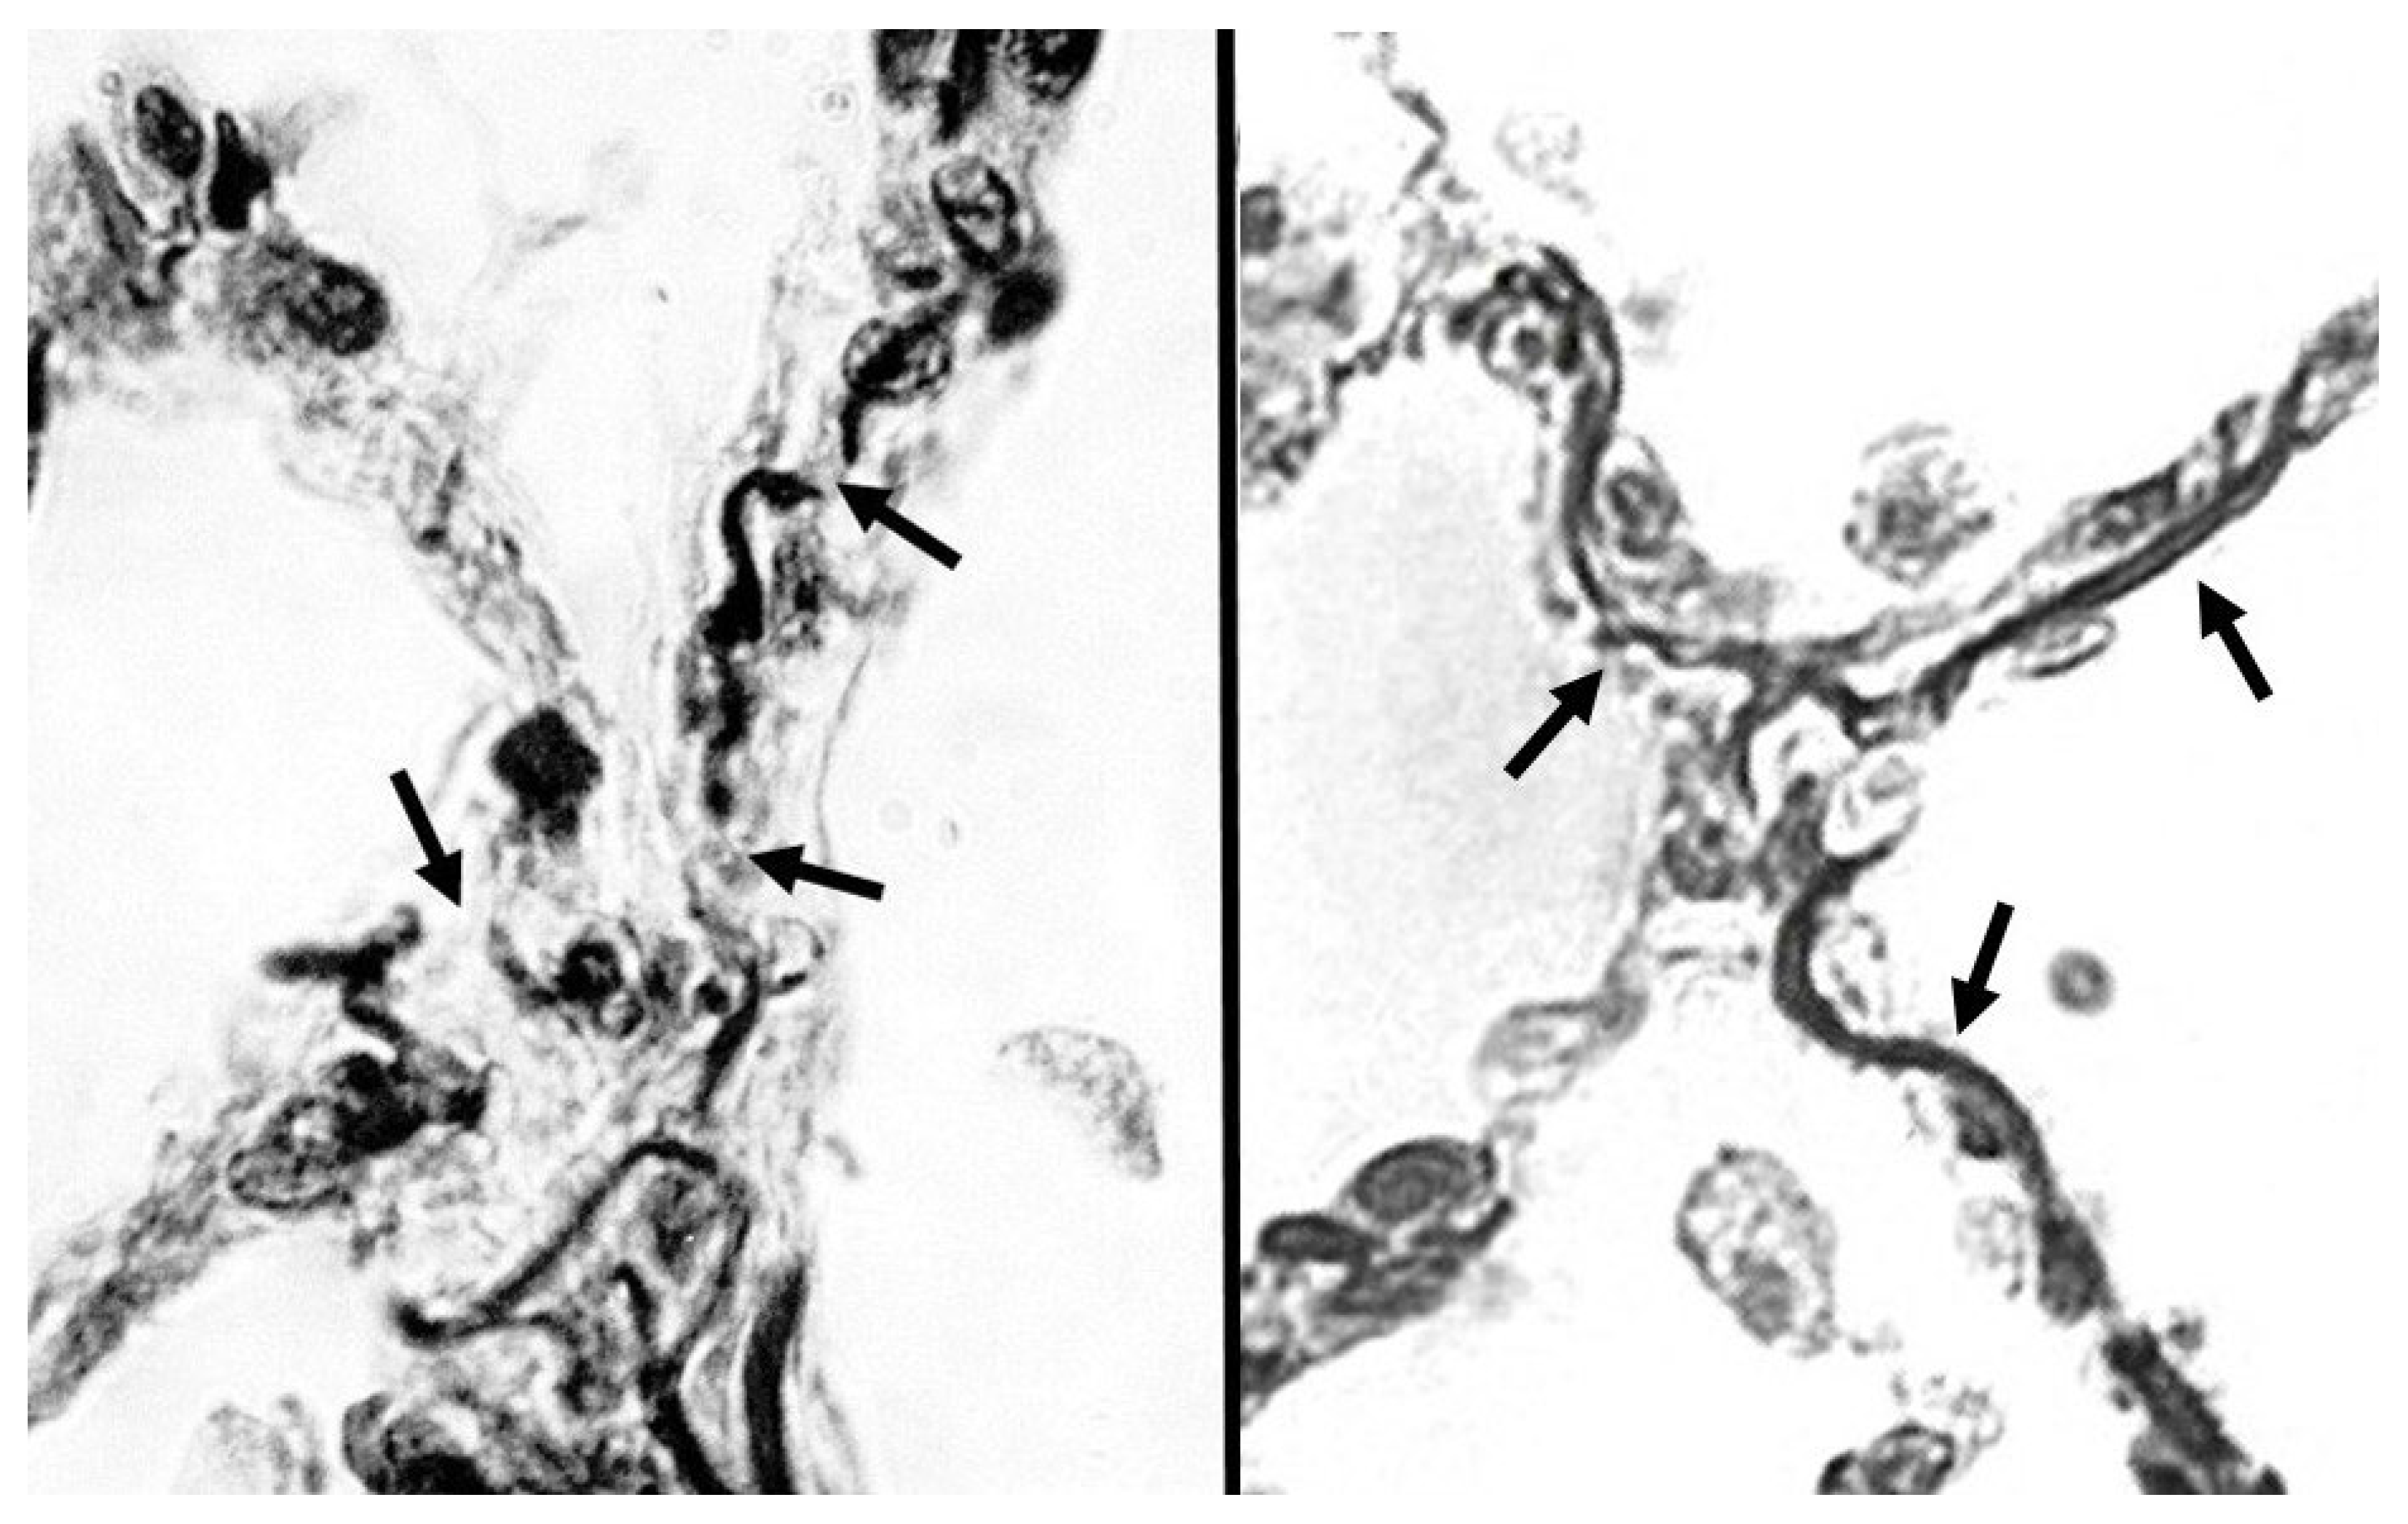

3. Fragmentation of Hypercrosslinked Elastic Fibers

- Fagiola, M.; Reznik, S.; Riaz, M.; Qyang, Y.; Lee, S.; Avella, J.; Turino, G.; Cantor, J. The relationship between elastin cross-linking and alveolar wall rupture in human pulmonary emphysema. Am. J. Physiol.-Lung Cell. Mol. Physiol. 2023, 324, L1–L10. [Google Scholar] [CrossRef]